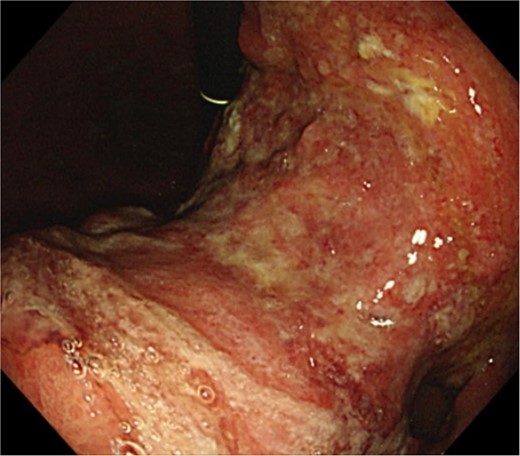

An 83-year-old man visited due to discomfort in the stomach. The patient underwent upper endoscopy that revealed a large tumor in the stomach (Fig. 1). The histological diagnosis was moderately differentiated tubular adenocarcinoma. Computed tomography (CT) revealed thickening of the gastric wall and bulky lymph nodes around the pancreas (Fig. 2). The patient underwent subtotal gastrectomy with Roux-en-Y reconstruction. The metastatic lymph nodes around the pancreas were removed. Abdominal drainage from Winslow’s foramen was performed. The pathological result was pT4aN3aM0 and Stage IIIB [1].

Clinical findings of contrast-enhanced CT. CT revealed the thickness of gastric wall and enlarged lymph nodes of lesser curvature side.